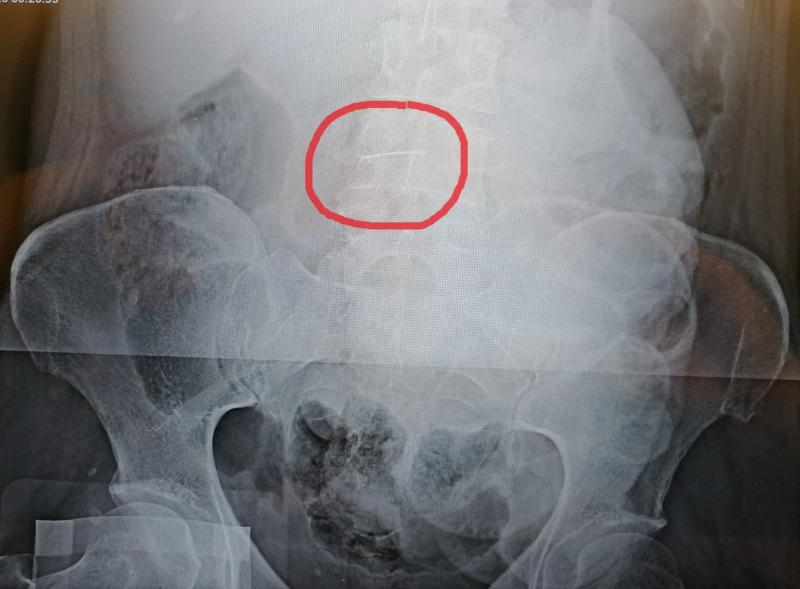

«В один из дежурных дней женщину по экстренным показаниям скорой помощью доставили с подозрением на желудочно-кишечное кровотечение, данный диагноз в результате проведенного обследования не подтвердился, - заявили в Комитете здравоохранения Волгоградской области. - Проведя обзорную рентгенографию, врачи выяснили, что в брюшной полости у пациентки находится швейная игла, представляющая смертельную опасность».

«Иглу, которая пробыла внутри тела пациентки почти 20 лет, обнаружили как случайную находку. Не иначе как «мина замедленного действия», игла в любой момент могла начать двигаться внутри брюшной полости и привести к смертельным повреждениям, но благодаря профессионализму хирургов больную удалось спасти, - рассказали в облздраве. - Операция прошла успешно, хирурги, под рентгеновским контролем извлекли иглу длинной 5 см, к счастью она не успела повредить жизненно важные органы, в настоящее время пациентка идет на поправку».

Врачи нашли убедительным такое объяснение и сделали следующий вывод: «Пациентка получила травму, в результате которой игла попала в брюшную стенку, а затем мигрировала в брюшную полость и застряла в сальнике», - резюмировали в волгоградском облздраве.